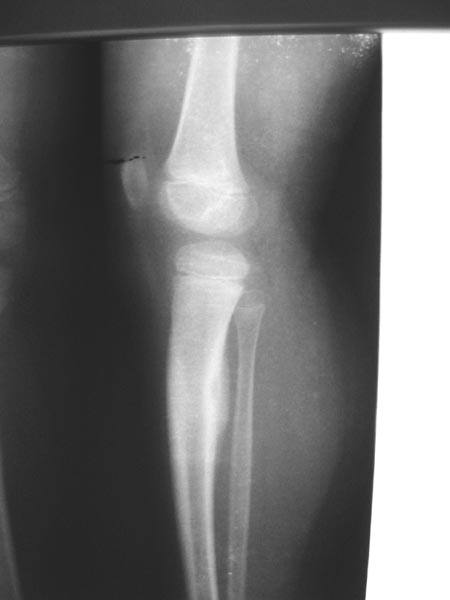

以下是引用岩光蛋在2007-3-4 23:41:00的发言:[br]右胫骨上段骨干后侧骨皮质增厚,中心部位可见一小椭圆形透亮区,考虑为瘤巢,故考虑骨样骨瘤,如果服用水杨酸类药物可解除疼痛则进一步验证此诊断。

以下是引用jiajie在2007-3-4 18:52:00的发言:[br]局部骨皮纸增厚,骨髓腔密度增高,骨膜增厚,一月前右小腿有外伤史,考虑外伤诱发骨髓炎。